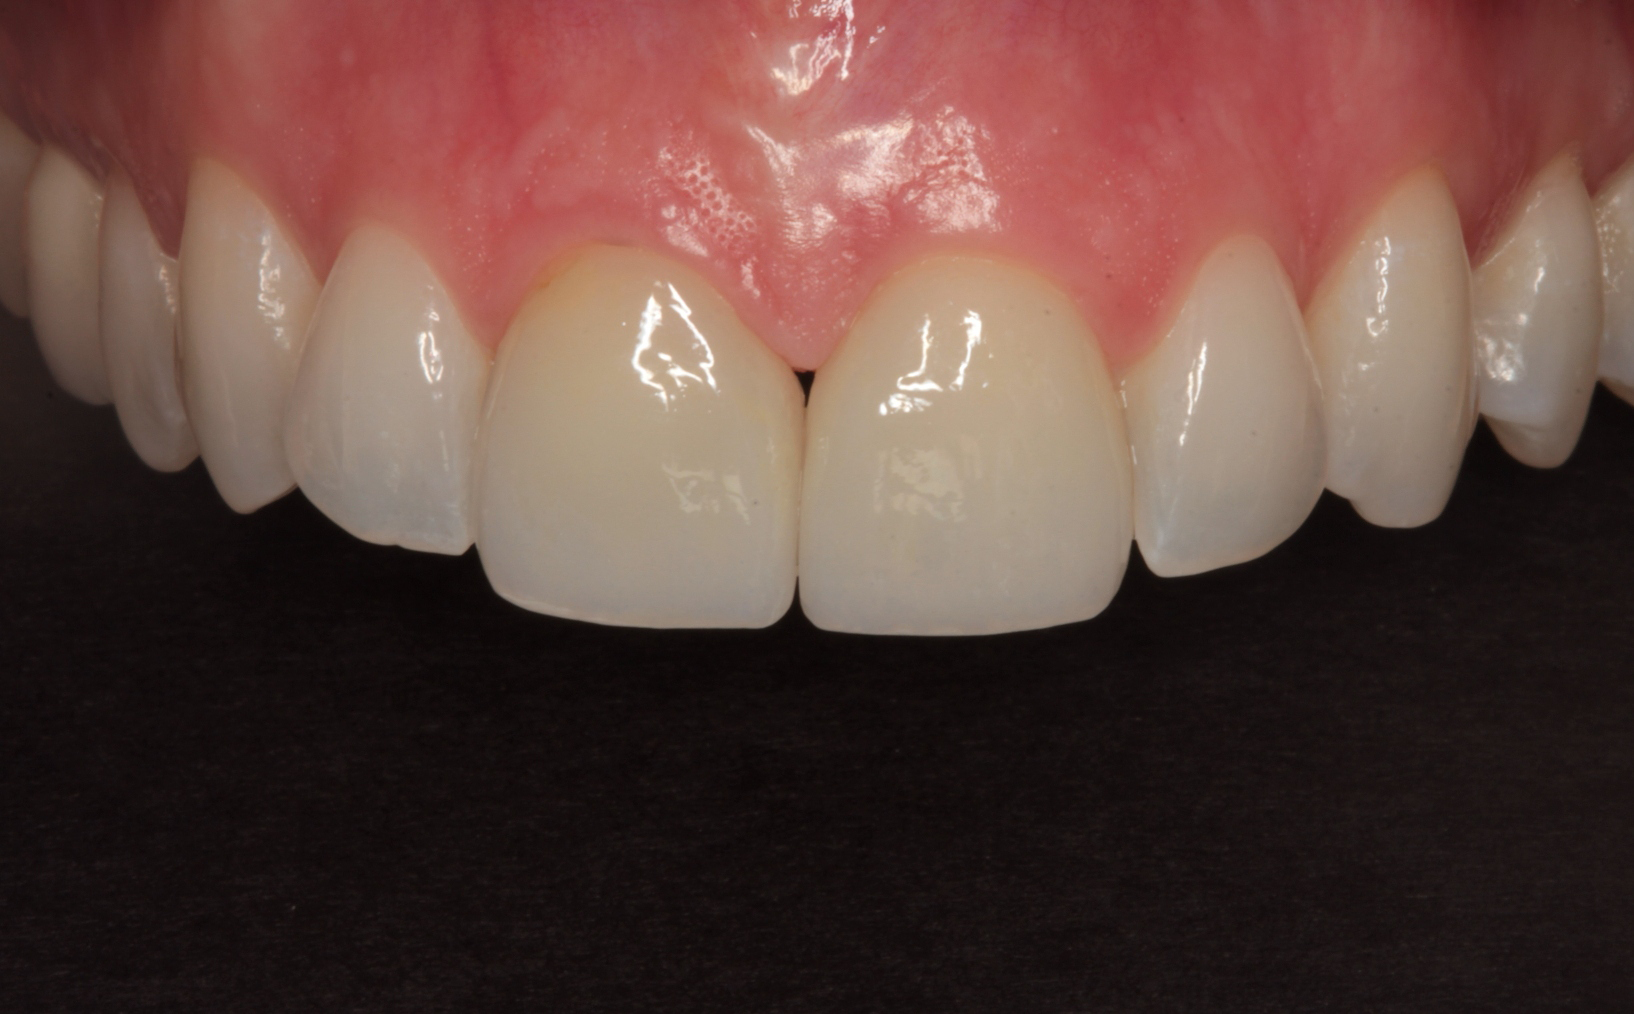

Figure 1 is a facial view of the first veneers in place. In the incisal view (Fig. 2), you can see that the veneers were used to close a central diastema. The reading from Vita Shade Light showed that the lateral incisors were 1M1 on the Vita 3D Shade Guide (Fig. 3).

Fig. 1 Fig. 2